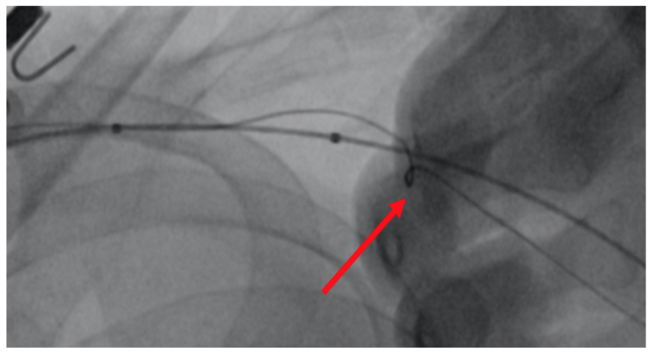

A 64-year-old female presented for closure of her left axillary access for intra-aortic balloon pump (IABP). We intended to close the access with standard balloon-assisted dry closure. A 7-Fr slender radial sheath was placed via left radial artery with a 7-mm peripheral balloon (Admiral; Medtronic) advanced to the subclavian artery. The IABP was removed over an 0.025-inch J-wire. There was already kinking noted at the entry site as indicated (Figure 1) due to adverse angulation. We failed to advance a Proglide device (Abbott) over an 0.035-inch wire due to kinking at transition zone of soft and hard part of the Proglide device (Figure 2).